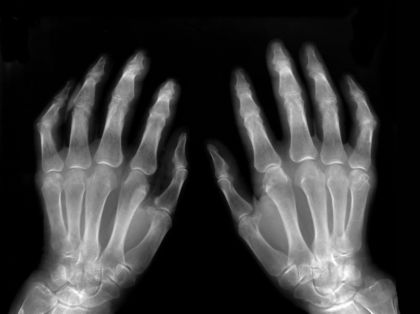

The sensitivity of various types of cells is shown below. The dose given in each case is the lowest amount of radiation that cells in the tissue can absorb without being damaged:

- Fetus: 2 Gy

- Bone marrow: 2 Gy

- Ovaries: 2–3 Gy

- Lens of the eye: 5 Gy

- A child's bone: 20 Gy

- An adult's bone: 60 Gy

- A child's muscle: 20–30 Gy

- An adult's muscle: 100 or more Gy